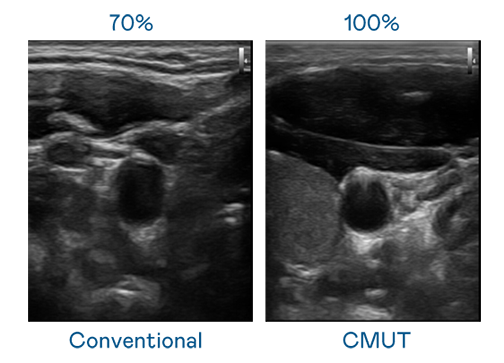

CMUT 技術是一種用電容式微機電元件來產生超音波訊號的技術。與傳統 PZT 壓電式技術相比,CMUT 頻寬增加 30%,更寬頻的超音波訊號讓影像解析度大幅提升,是實現高影像品質醫療超音波掃描、促進精準醫療發展的關鍵技術。

超音波影像的解析度高低,首先取決於探頭能發出的訊號頻寬。极速快3 CMUT 可提供高清晰的超音波訊號,提供高頻寬、高靈敏度、影像紋理細節更高的超音波影像,協助醫護人員縮短影像判讀時間及利用精準的醫療影像進行診斷。